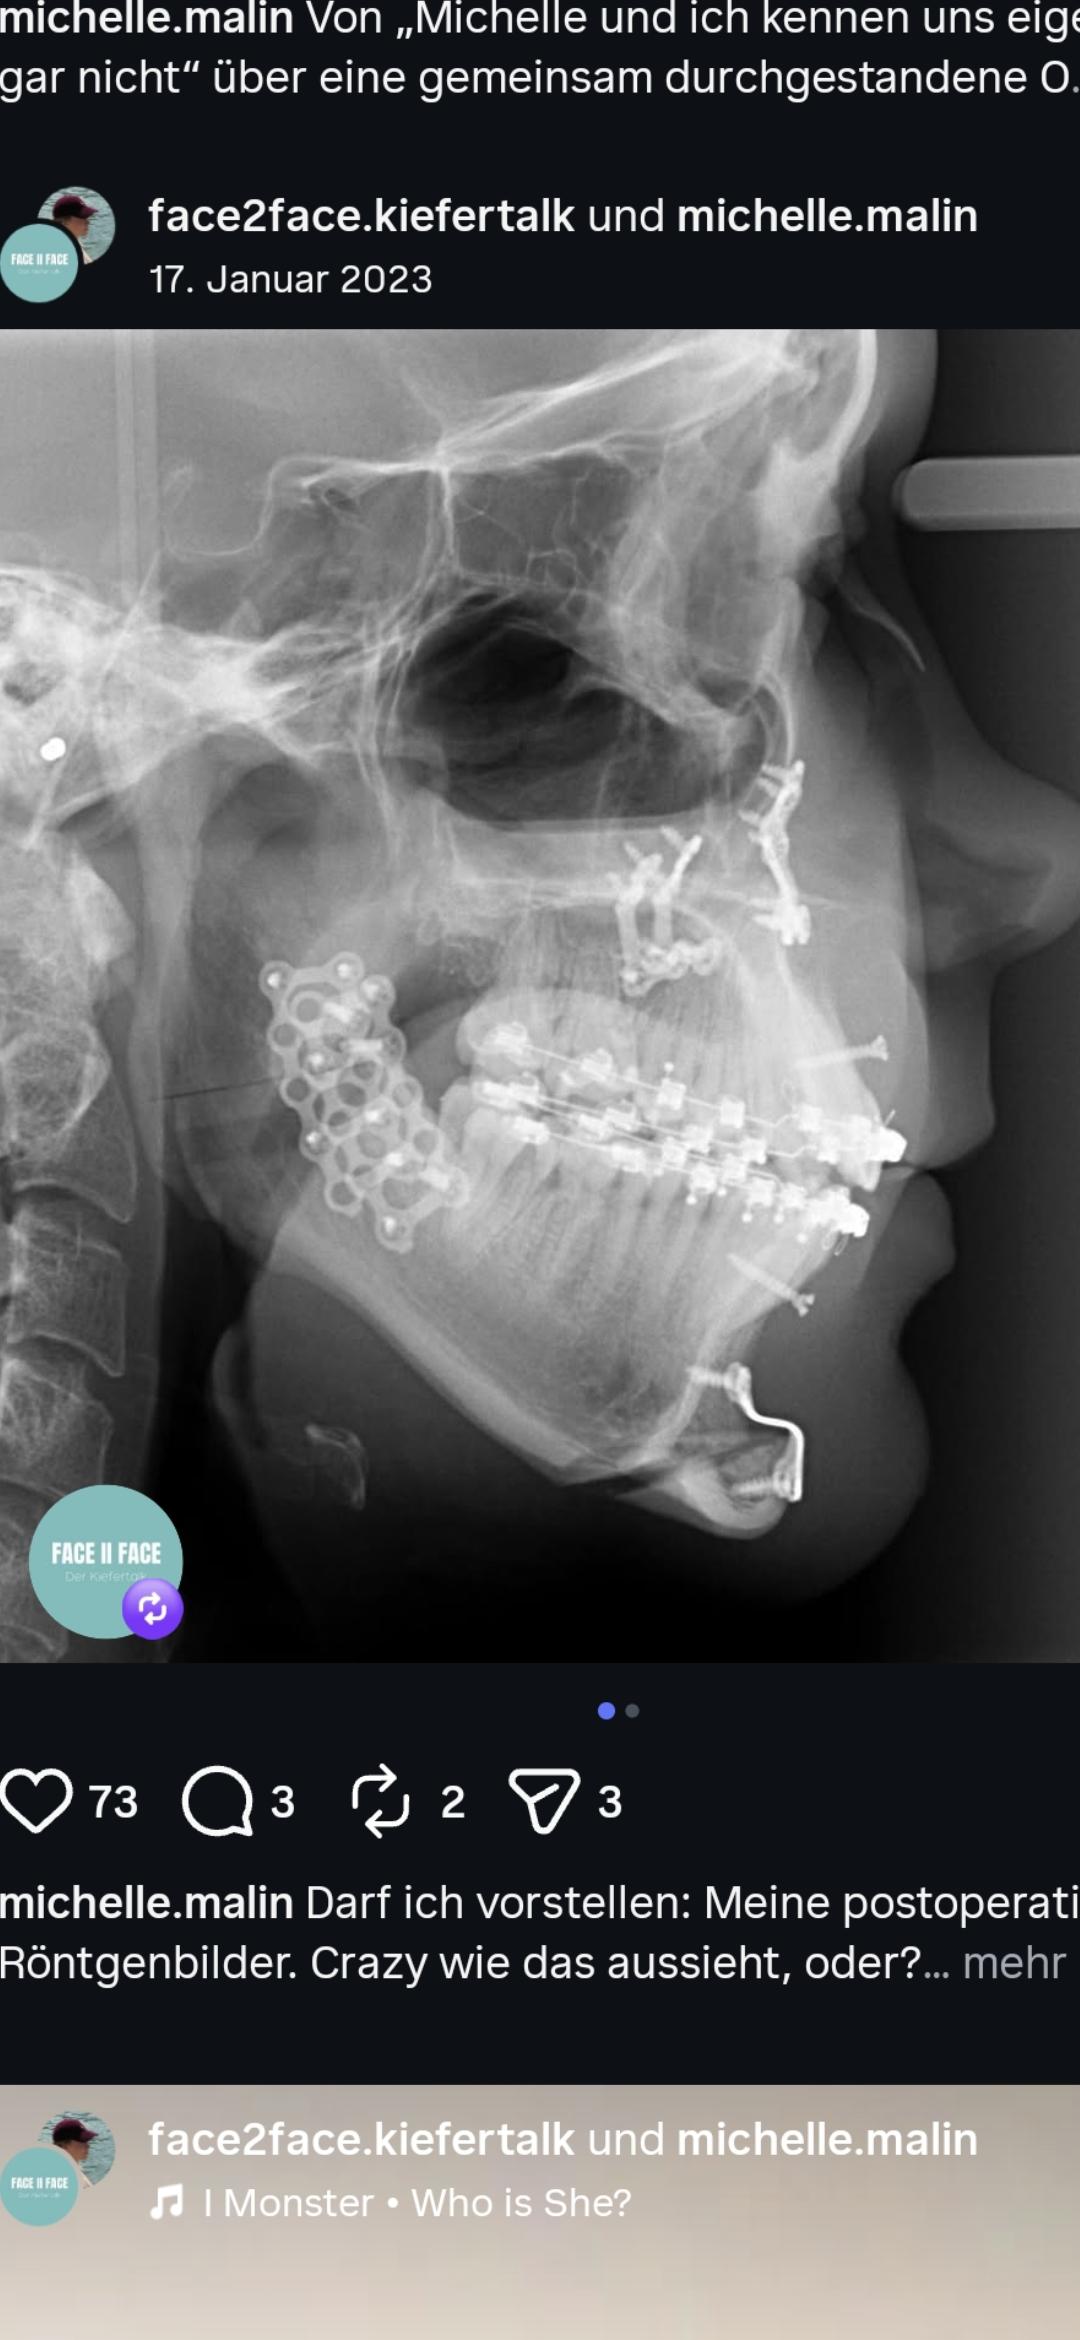

I can't see the lateral cut? There`s a large cut below the condyles above the ramus, but i can't see the lateral cut behind the bottom teethrow? Can someone explain this cut to me?